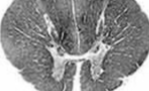

throacic

knowt flashcard image